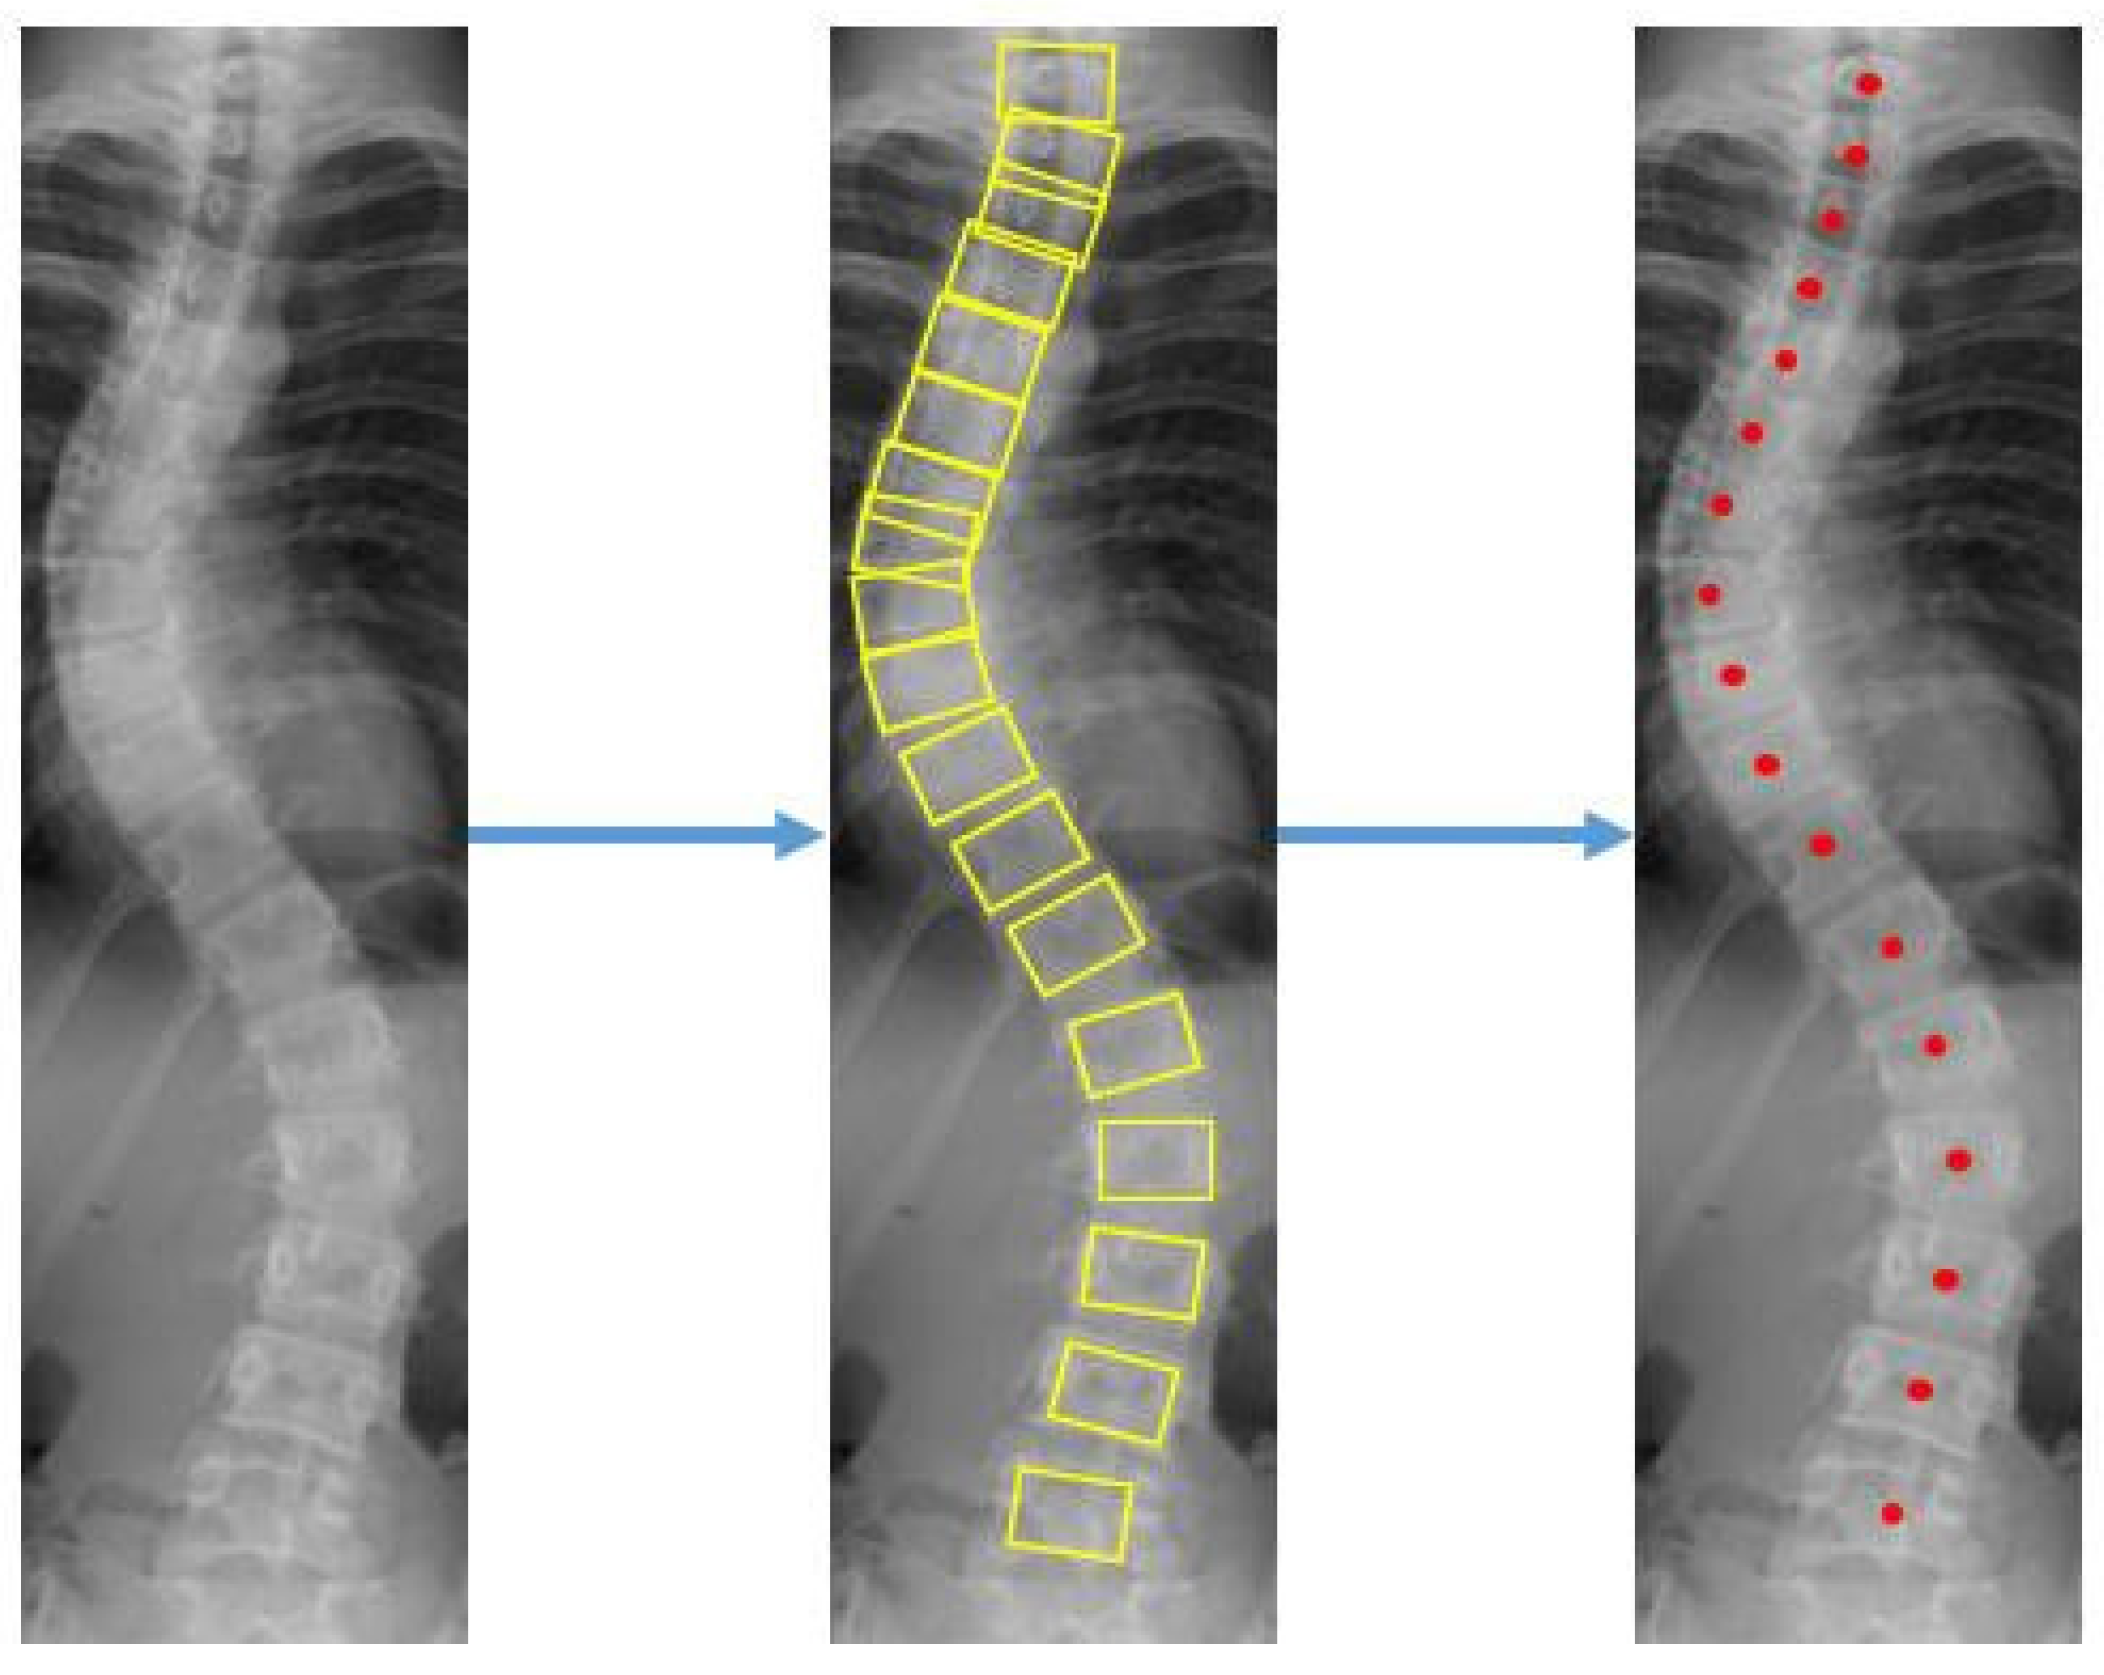

Patients with AIS who attended the scoliosis clinic at Pantai Jerudong Specialist Centre from 1 November 2018 to 4 September 2020 were identified from the institution’s scoliosis database. These patients had standard standing anterior-posterior X-rays showing cervical vertebra level 7 to the femoral heads and the entire rib cage from right to left as part of routine clinical management. The X-ray images were retrieved from the institution PACS, anonymized, and exported as a JPEG format image, as shown in Figure 2. The CA for each X-ray image was measured by (1) two neurosurgeons (Observer 1 specializes in scoliosis; Observer 2 does not), who were blinded to each other and the ACAMM, using the in-built function in the PACS and (2) the ACAMM.

Figure 2.

Examples of standard X-ray images exported from the PACS: (a) CA < 10°; (b) CA 10° to 25°; (c) CA > 25° to 40°; (d) CA > 40°.